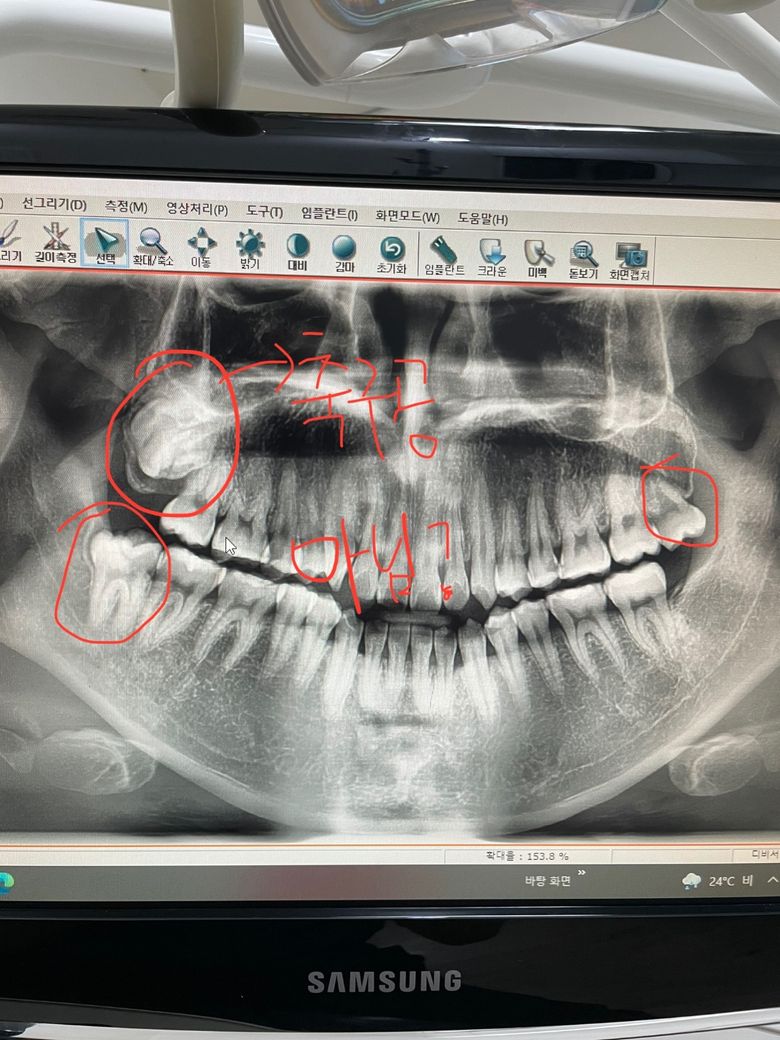

왼쪽 상단에 도저히 사람의 이로 보이지 않는데 이건 안뽑는게 낫나여? 교정하고 싶은데 보통 사랑니는 전부 발치한다고 알고 있어서 질문드립니다

사랑니는 치아형태가 기형인 경우 종종 있습니다. 지금은 치아가 뭉쳐 보이는 치아종일 가능성도 있습니다.어쨌거나 이런 경우는 수술로 뽑아 확인하는 것이 좋습니다.

사진에 보이는 사랑니는 잇몸뼈 깊숙히 매복되어 잇어서 특별한 이유가 없다면 발치를 하지 않으셔도 됩니다.

치조골안에 매복되어 있는 사랑니는 굳이 발치를 하지 않아도 됩니다.

나머지 치아는 발치를 하는데 크게 어려움이 있지는 않으나 오른쪽아래 사랑니의 경우에는 사랑니의 뒷편에 치조골이 있어 발치를 하는 데 시간이 좀 걸릴수 있습니다.

모양이 이상하다고 특별히 발치 난이도가 확 높아지거나 그런건 아닙니다